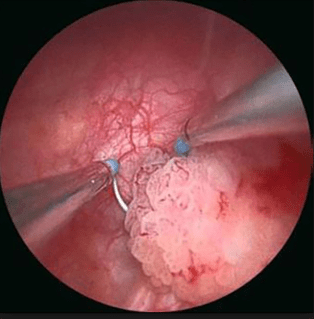

URETROCISTOSCOPIA

Consiste en la introducción de un Uretrocistoscopio a través del meato uretral y que permitirá la valoración de la uretra y de la vejiga. Aunque la mayoría de lesiones malignas vesicales son bastante bien reconocidas, el urólogo deberá tener alguna experiencia para determinar la presencia de lesiones sospechosas de Cáncer In Situ u otras lesiones menos comunes y benignas (Cistitis folicular, cistitis inespecífica, etc) que puedan ser causa de hematuria.

![]() |

| En general, las lesiones malignas más frecuentes son fácilmente reconocidas sin embargo existen otras que pueden hacer dudar del diagnóstico. Es importante el estudio de imágenes en cistoscopia. |